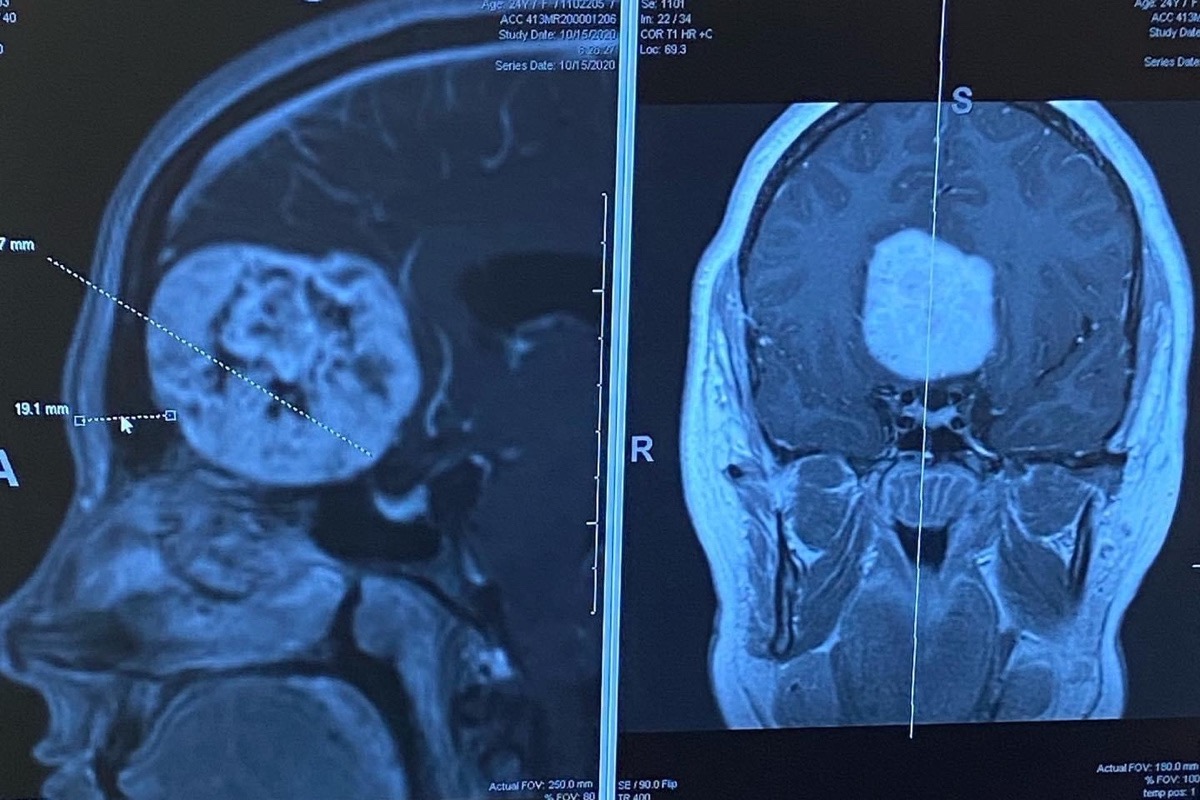

Ashlee will have to undergo a very dangerous brain surgery due to this brain tumor that has been growing for years and just recently a doctor has caught it. She refuses to ask for money so I took it upon my self to start this go fund me, she will be out of work for 3 months at least and although she has amazing support through her family, they do not have the funds to be able to pay her bills. She has an almost 4 year old boy she also need to support. Anything will help. And if you cannot donate, please send thoughts/prayers/hope, however you choose to manifest positivity.